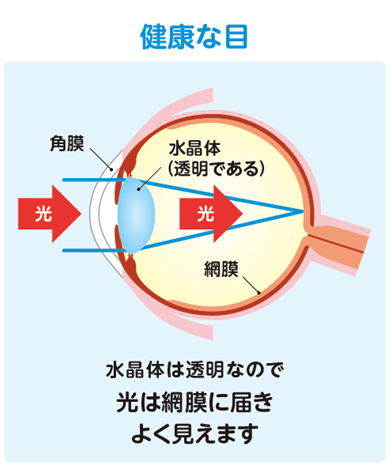

白内障について

目の中の水晶体が濁り、光が通りづらくなりみえづらくなる状態です。